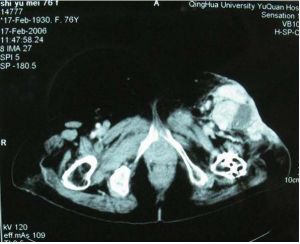

2、CT檢查軟組織惡性纖維組織細胞瘤CT圖像表現為密度均一的腫塊。骨內惡性纖維組織細胞瘤CT影像的差異較大,可以觀察到腫塊自骨破壞中心向四周組織中蔓延,多呈分葉狀,無完整包膜,軟組織腫塊有時巨大,呈低密度浸潤狀生長,邊緣不清,腫物中心常有壞死囊變區。

本組52例,男33例,女19例;年齡最大75歲,最小12歲,平均年齡48.7歲。病史3個月~5年,平均病史6.8個月。本組中BMFH主要以局部疼痛、腫脹及腫塊為主訴,主要發生於膝關節和肩關節周圍(分別32例和14例,約占88%),股骨近端3例,跟骨、腰椎、髂骨各1例。術前行X線片52例,CT49例,MRI48例。X線及CT以溶骨性骨質破壞為主,常伴有軟組織包塊,MRI清楚的顯示腫瘤侵犯的範圍。

患者,女,52歲,左脛骨BMFH。術前X線片及CT示脛骨斑片樣、蟲蝕狀骨破壞,周圍由硬化邊緣(略) MRI示腫瘤侵犯的範圍、軟組織包塊及周圍比鄰的關係(略)

BMFH由於缺乏特殊的影像學表現,故不能根據術前X線片、CT、MRI明確診斷,但影像學檢查可以幫助診斷,並且對確定手術方案有很大幫助。根據本組資料,作者總結BMFH影像學表現:(1)X線表現:BMFH的X線表現多種多樣,特徵性少。以蟲噬狀、斑片狀或大片狀溶骨性破壞為主,邊界不清,少數可有邊緣硬化,常伴有軟組織腫塊,骨膜反應無或輕微,這是BMFH的重要特點。(2)CT表現:更清楚地顯示骨質破壞和軟組織腫塊,骨質破壞同X線,少數病灶為囊狀或膨脹性,內有粗條索狀及格線狀嵴,並見邊緣硬化,類似良性病變,骨膜反應少見。(3)MRI表現:BMFH的MRI表現缺乏特異性,但其對腫瘤髓內侵犯、周圍邊界可清楚顯示,指導手術切除範圍,還可顯示腫瘤與鄰近血管的關係以及判斷腫瘤術後改變與術後復發等方面優於X線及CT。